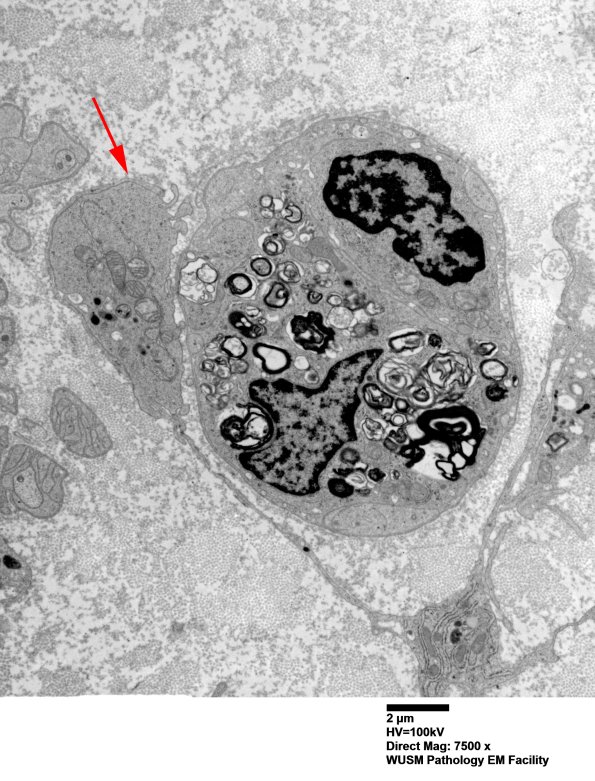

2A-E Early Contact of Macrophages with Schwann cells containing axon and myelin debris. ---- 2A An early contact of a macrophage with degenerating myelin and axonal debris enclosed within a Schwann cell likely represents an early phase of transfer between the cells.